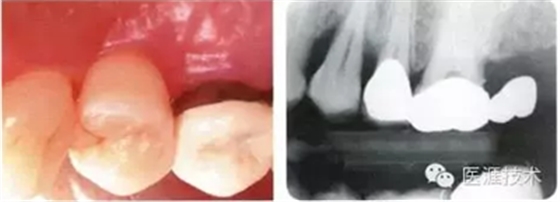

初期治療后左上4的近中有牙槽骨吸收三角區(qū)的凹凸,目前堅(jiān)持進(jìn)行維護(hù)的狀態(tài)下牙周袋深度仍有6mm。菌斑控制做得很好,牙齦組織緊繃健康,沒有出血現(xiàn)象。